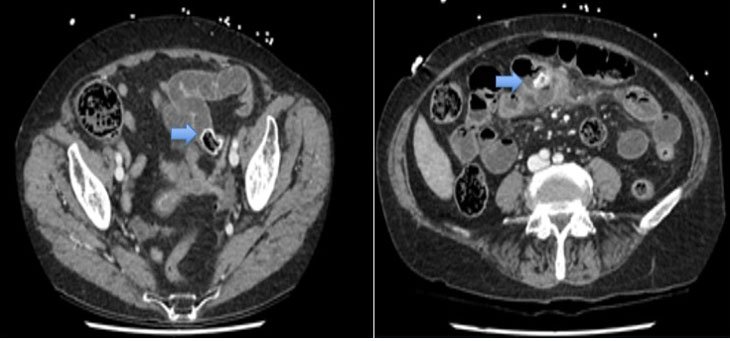

This 75-year-old female presented to a regional hospital and was subsequently transferred to our institution for assessment by the general surgical team. She was complaining of severe sudden onset abdominal pain for one day associated with multiple episodes of vomiting and had been getting worse. On examination she was hemodynamically stable and the abdomen was distended and diffusely tender. Biochemical markers were unremarkable. Subsequent CT scan revealed a jejunal diverticulitis with largest diverticulum containing a large mixed density structure, in keeping with an enterolith. The adjacent diverticulum no longer contained an enterolith which was seen on a previous CT (Figure 1). Evidence of small bowel obstruction noted with abrupt transition at the level of the left pelvic brim secondary to the migrated enterolith. Pelvic and interloop free fluid was also noted. She was managed with a nasogastric tube and fluid resuscitation and proceeded for an emergency laparotomy.

Figure 1: Coronal views of CT demonstrating an enterolith causing small bowel obstruction and another enterolith within the diverticulum.